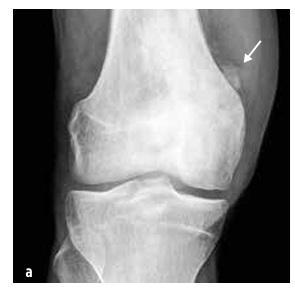

Код деце најчешћи типови су остеосарком (55%, видети Слику 5) и Јуин сарком (35%, видети Слику 6), док је хондросарком изузетно редак. У ову групу такође спадају саркоми меких ткива (рабдомиосарком и нерабдомиосаркоми), мезенхимални ћелијски тумори, екстраскелетни Евингов сарком, синовијални сарком, фибросарком и ембрионални сарком.

Слика 5

Остеосарком дисталног дела бутне кости